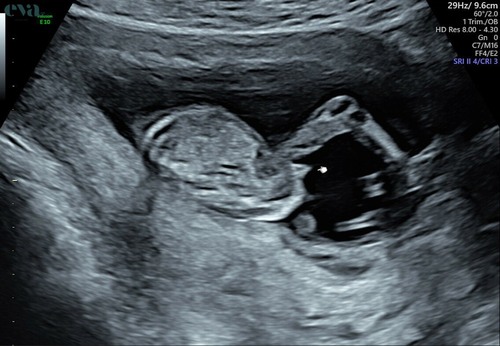

Hee allemaal, zojuist een echo gehad op 13+4. Ik weet niet zo goed of dit een goede foto is voor de nub.. iemand die een gokje kan wagen op basis hiervan? 🥰💖🩵

Reactie op RW90

Hee allemaal, zojuist een echo gehad op 13+4. Ik weet niet zo goed of dit e ...

Meisje

Ik denk een meisje